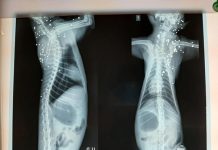

Gato morre com mais de 100 perfurações de tiros em Rio Preto

Um gato foi resgatado após ser encontrado com mais de 100 perfurações causadas por disparos de arma de fogo, em São José do Rio...